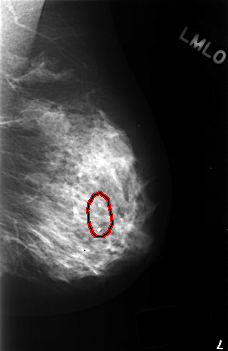

FILE: C_0407_1.LEFT_MLO.OVERLAY

TOTAL_ABNORMALITIES 1

ABNORMALITY 1

LESION_TYPE CALCIFICATION TYPE DYSTROPHIC DISTRIBUTION SEGMENTAL

ASSESSMENT 2

SUBTLETY 5

PATHOLOGY BENIGN_WITHOUT_CALLBACK

TOTAL_OUTLINES 1

BOUNDARY